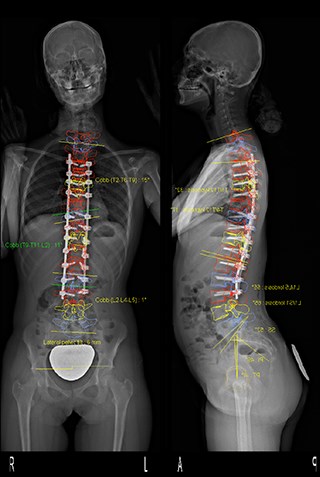

Измерение кифоза грудного отдела: Рентгеновские снимки